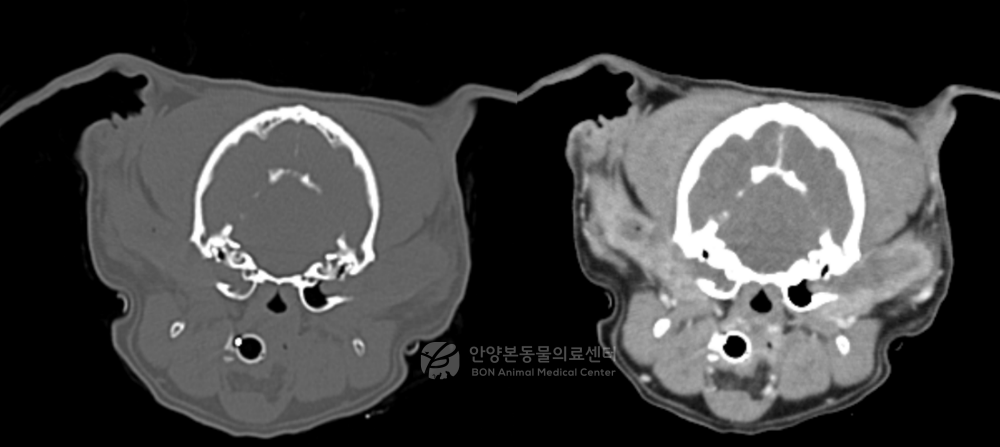

영상 검사 및 진단

외이염이 만성화된 경우에는 겉으로 보이는 상태만으로는 실제 병의 진행 정도를 정확히 판단하기 어렵습니다. 특히 중이염이 같이 있는지, 이도 석회화가 어느 정도인지, 외이도 안쪽 구조가 얼마나 변형되었는지 확인하는 것이 중요합니다. 이번 환자에서는 이를 위해 CT 검사를 진행했습니다.

CT 검사에서 확인된 점

• · 양측 외이도 석회화

• · 외이도 증식성 변화

• · 우측 중이염

• · 고실 내부 삼출물

이러한 소견은 단순 외이염이 아니라 만성 외이염이 구조적으로 진행되어 중이염까지 동반된 상태를 의미했습니다.

이 환자의 케이스는 더 이상 내과적 치료만으로는 호전을 기대하기 어려운 단계로 판단할 수 있었습니다.

강아지 외이염 CT 검사 결과

[CT 검사 결과]